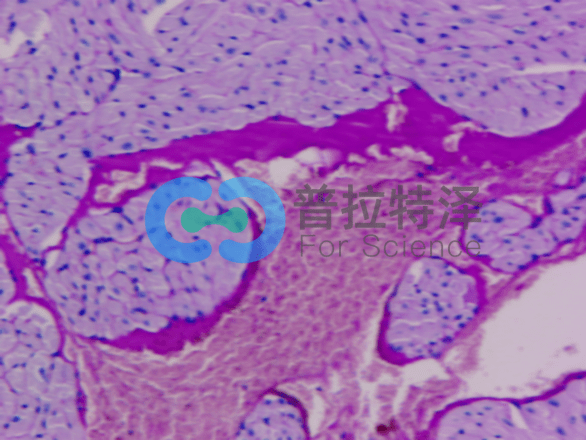

[圖2]

二、細(xì)胞類(lèi)型和結(jié)構(gòu)

PAS染色不僅可以顯示多糖類(lèi)物質(zhì),還可以揭示細(xì)胞的類(lèi)型和結(jié)構(gòu)。例如,在某些病理狀態(tài)下,某些細(xì)胞可能會(huì)過(guò)度分泌多糖類(lèi)物質(zhì),導(dǎo)致染色結(jié)果異常。通過(guò)觀察這些細(xì)胞的形態(tài)和分布,我們可以進(jìn)一步了解疾病的發(fā)病機(jī)制和進(jìn)展過(guò)程。